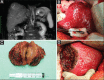

Figure 3

Magnetic resonance imaging (A), operative field before (B) and after hepatectomy (D) as well as operative specimen (C) of a patient with hepatocellular carcinoma in segment VII in cirrhosis undergoing open hepatectomy